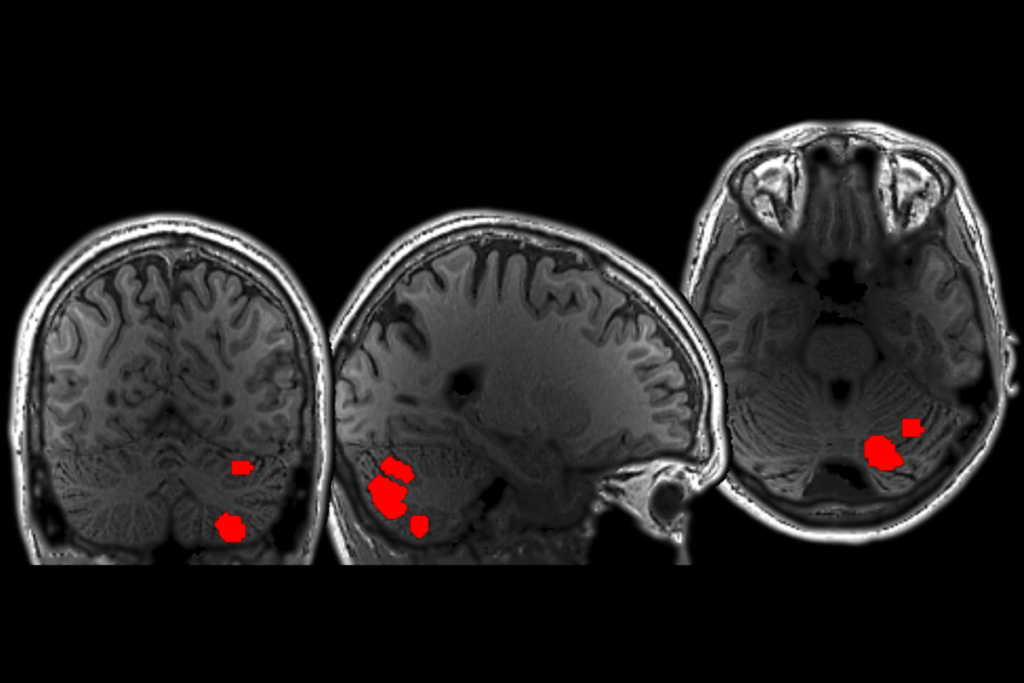

Zoghbi and her team surgically implanted electrodes in the brains of female mice missing a copy of the MeCP2 gene, which is mutated in people with Rett syndrome. They positioned the electrodes to stimulate a nerve bundle that connects to the brain’s memory center, the hippocampus.

The researchers stimulated the this nerve bundle in the mice for an hour each day for two weeks. Control mice missing MeCP2 were implanted with electrodes but did not receive stimulation.